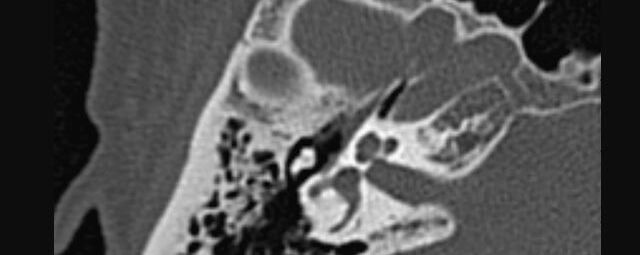

• Nasennebenhöhlen (Entzündungen, Tumore)

Thorax (Brustkorb)